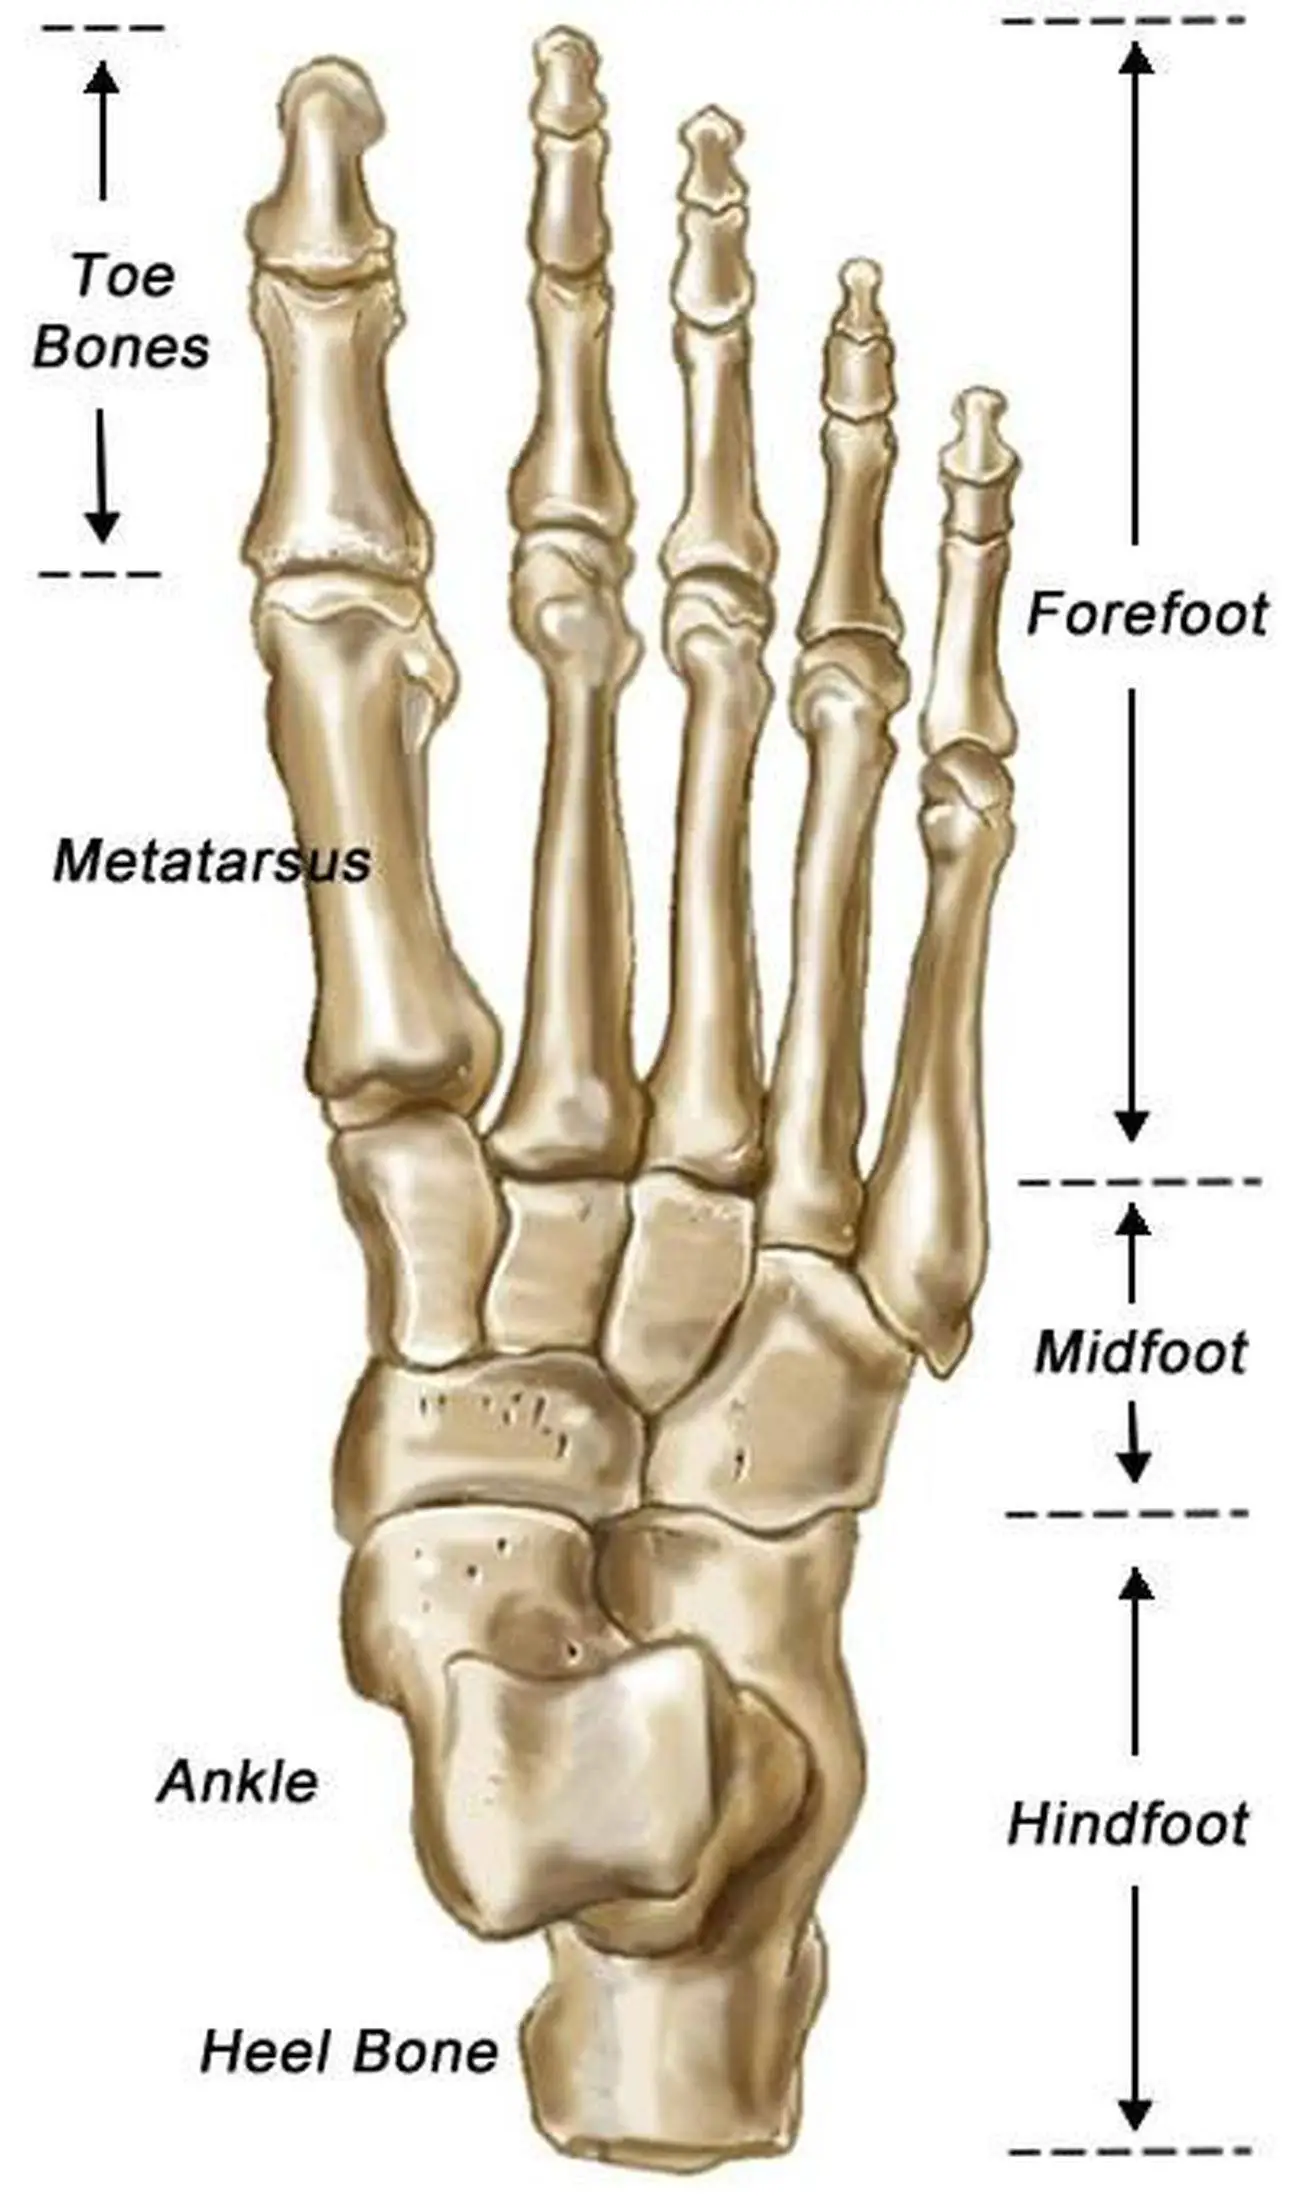

Anatomia Delle Ossa Dei Piedi Illustrazione Di Stock - Illustrazione Di

it.dreamstime.comFoot Bones With Explanation. Stock Vector - Image: 65669090

it.dreamstime.comFoot Bones With Explanation. Stock Vector - Image: 65669090

Piede E Avampiede: Anatomia, Funzioni E Patologie In Sintesi | MEDICINA

medicinaonline.copiede osso scafoide anatomia cuboide ossa metatarso tarsale patologie funzioni avampiede tarso mediale caviglia netter articolazione processo accessorie prossimale falangi

medicinaonline.copiede osso scafoide anatomia cuboide ossa metatarso tarsale patologie funzioni avampiede tarso mediale caviglia netter articolazione processo accessorie prossimale falangi